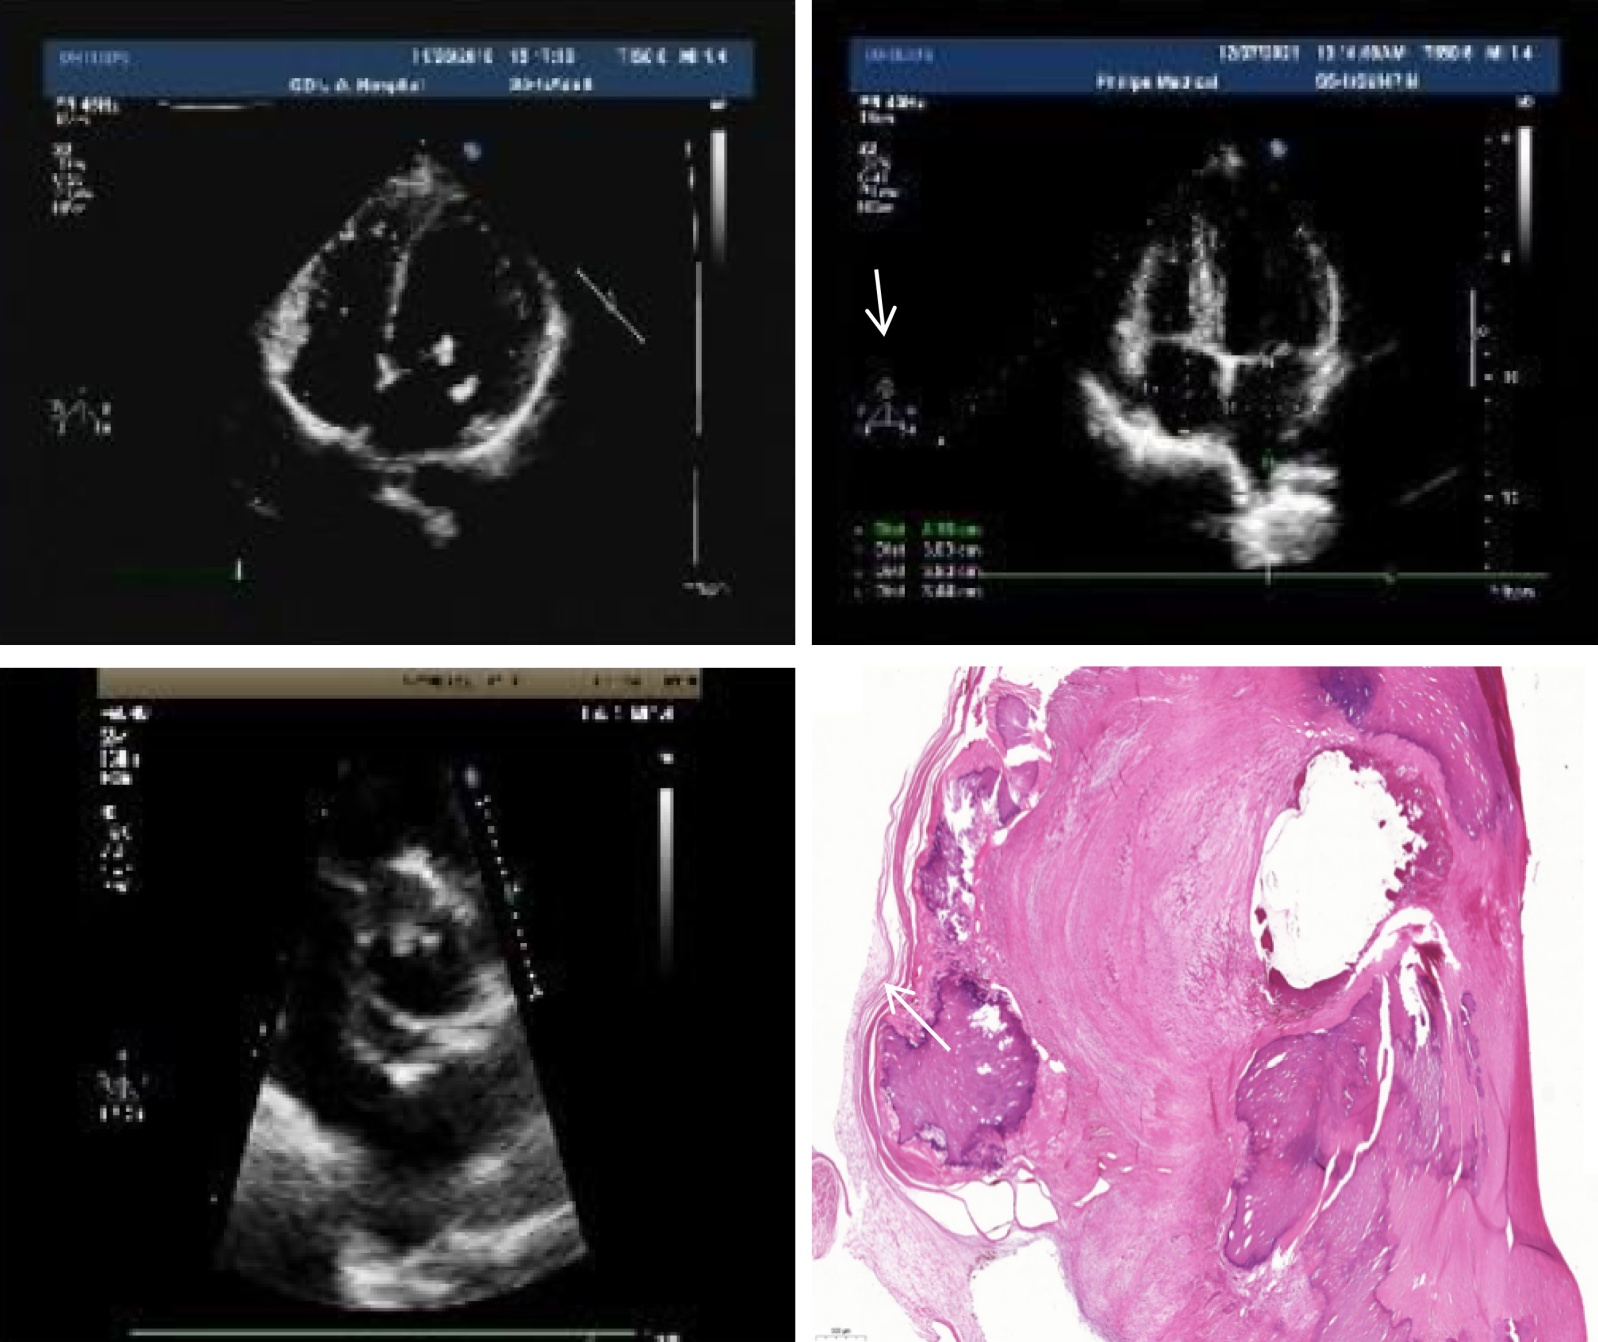

10例患者9例更换生物瓣,1例更换机械瓣,1例行二尖瓣联合主动脉瓣生物瓣置换术。术中可见瓣膜局灶或弥漫水肿增厚、瓣叶畸形、钙化及赘生物形成,并累及瓣膜下结构,腱索断裂,主动脉根部受累,造成主动脉根部管壁钙化及扩张。术后病理结果提示瓣膜长期、慢性、炎性损伤(图1表3表4)。

A. 二尖瓣瓣尖显著增厚,A3、P2、P3区见团状钙化(赘生物);B. 主动脉瓣瓣叶不规则增厚;C. 主动脉瓣前叶可见数个中低回声附着;D. (二尖瓣及赘生物)增生的纤维胶原伴钙盐沉积,部分区域可见纤维素样坏死、间质粘液变。

Figure 1. Echocardiographic characteristics of patients

1. 患者的超声心动图特征